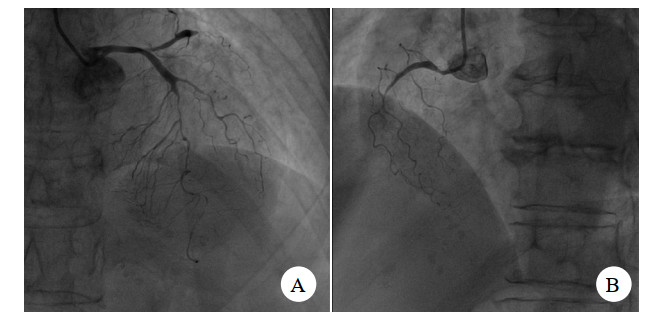

入院后考虑患者起病11 h,仍有胸痛,且心电图Ⅱ、Ⅲ、avF ST段上抬,故有急诊介入治疗手术指征,遂与患者家属交代病情,签署知情同意书后安排急诊介入手术。急诊介入过程见图 2、图 3。

| 图 2 患者急诊造影检查图像 |

患者冠脉造影提示:①前降支中远端弥漫狭窄80%~90%,第一对角支:全程弥漫狭窄70%~80%,前降支及对角支远端TIMI血流2~3级;前降支逆向有侧支循环提供;②回旋支:近端狭窄85%,回旋支中段闭塞,钝缘支近端闭塞,TIMI血流0级;③右冠状动脉:中段以远闭塞,TIMI血流0级。考虑三支冠脉严脉痉挛。术中予去甲肾上腺素维持下予冠脉内注射硝酸甘油,硝普纳后患者冠脉痉挛解除,冠脉内注入尿激酶原20 mg抗栓,经处理后患者冠脉痉挛解除。